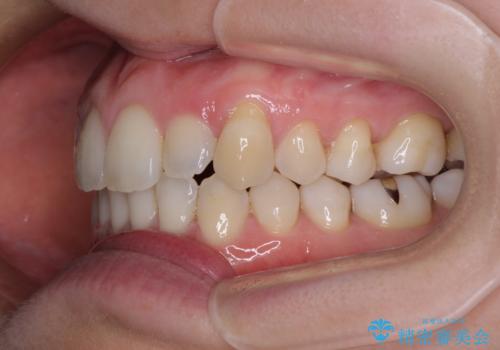

- 受け口傾向でクロスバイトの前歯を治したいとのことで来院された患者様です。

下顎骨が若干左側に変位していたため、右側にアンカースクリューを使用し、積極的に移動させながらインビザラインにて矯正治療を行うこととしました。

インビザラインによる矯正治療は、受け口傾向の治療に非常に適した方法であり、事前にシミュレーションに沿って治療を進めることできます。

今回の治療では骨格的な偏位があったためアンカースクリューを使用し、より確率の高い治療を行うことができました。